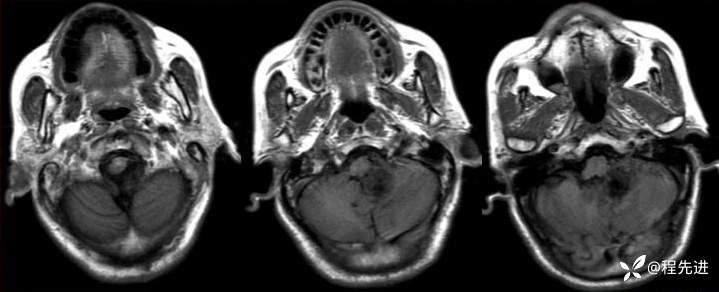

【患者信息】:男,66岁

【现病史及既往史】:头痛半年,行走不稳3个月

T2:

img